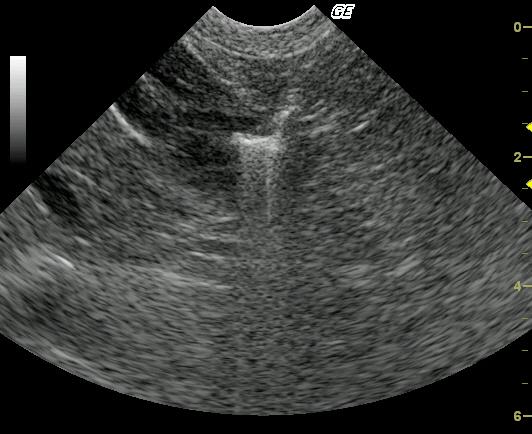

This 10 year old neutered male Beagle cross was presented for altered behavior. The physical exam was normal. CBC was normal while the blood chemistry revealed moderately elevated SAP and a slightly elevated total protein and slightly elevated globulin. The urinalysis revealed USG of 1.021 and 4+ proteinuria with inactive sediment. ACTH stimulation test was normal.